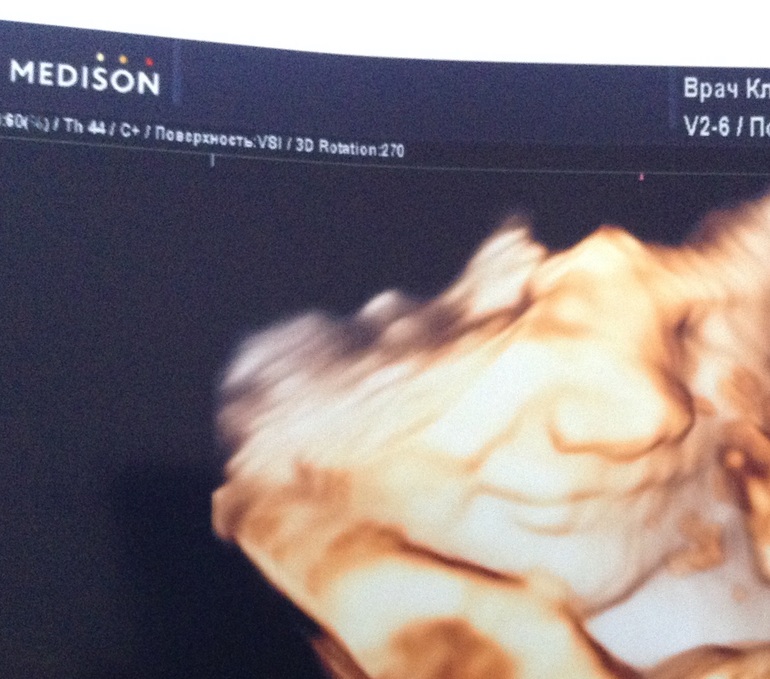

НЕ ПЕРВЫЙ малышдевочки ,всем спасибо кто отписывался на мои посты,сынок перевернулся,сегодня была на узи)))ура)))надеюсь назад не вернется,все таки не зря я в субботу еще икоту начала чуять внизу и пинки именно в боку .порадовал он меня вдобавок еще так мило улыбнулся)))всем желаю у кого на попе чтоб перевернулись ,но вообще по своему опыту скажу что девчонок родить и в тазовом можно легко ,я четвертую дочь родила очень легко ногами вперед ,легче даже чем в головном и речи о кс даж не шло ,и если б сын не перевернулся я б тоже сама рожать пошла бы ,особенно это актуально когда плод не большой и беременность не первая так что не переживайте

Боже ,какая улыбка)))))ещё и перевернулся!!!теперь будем держать кулочки до родов))))все теперь будет прекрасно,Катюш!!!